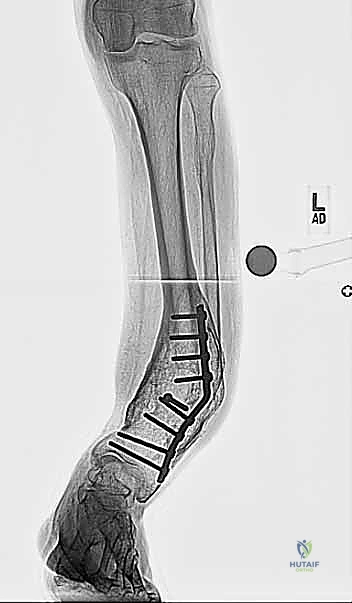

* أشعة سينية طولية للطرفين السفليين أثناء الوقوف (Standing Long-Leg X-rays): هذه هي الصورة الأهم. تسمح للطبيب برؤية محور الساق بالكامل من مفصل الورك، مروراً بالركبة، وصولاً إلى الكاحل.

فلسفة جراحة قطع العظم فوق الكاحل: لماذا هذا الموقع؟

كما ذُكر في الخلاصة الأولية، فإن اختيار مكان قطع العظم (Osteotomy Site) ليس عشوائياً. الفلسفة الأساسية التي يتبناها الجراحون الخبراء مثل الدكتور هطيف تعتمد على مبادئ بيولوجية وميكانيكية صارمة:

لماذا يتم القطع فوق الكاحل بحوالي 5 سم؟

1. الابتعاد عن العظم المتصلب (Sclerotic Bone): في نقطة التشوه القصوى (قمة التشوه الحقيقية)، غالباً ما يكون العظم كثيفاً جداً وضعيف التروية الدموية بسبب الإجهاد الميكانيكي المزمن. القطع في هذا المكان يؤدي إلى تأخر في الالتئام (Delayed Union) أو عدم الالتئام (Non-union).

2. استغلال منطقة الميتافيزيس الغنية بالدم: بنقل موقع القطع قليلاً إلى الأعلى (حوالي 5 سم فوق المفصل)، يتم القطع في منطقة ذات نسيج إسفنجي غني بالخلايا الجذعية والأوعية الدموية، مما يضمن التئاماً سريعاً وقوياً جداً وتكويناً ممتازاً للعظم الجديد (Regenerate Bone).

3. المساحة الكافية لتثبيت المسامير: يجب ترك مساحة كافية من العظم السليم بين مفصل الكاحل ومكان القطع لتثبيت أسلاك ومسامير المثبت الخارجي بقوة دون اختراق كبسولة المفصل.